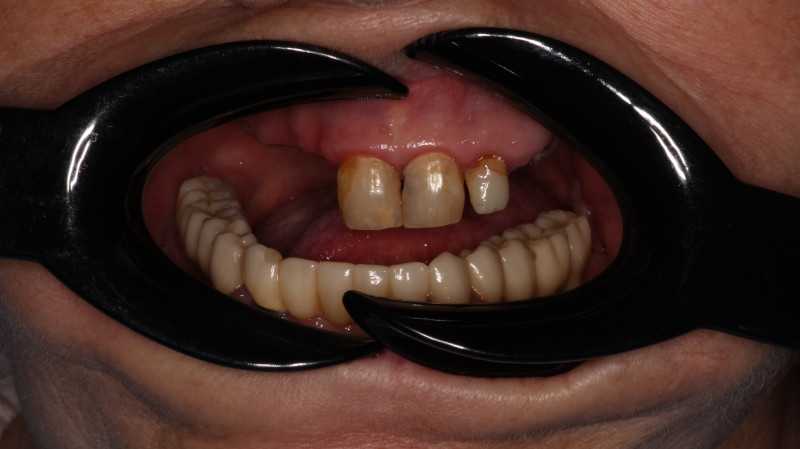

Жалобы: на отсутствие зубов, неудовлетворительную эстетику зубных рядов, невозможность жевать, подвижность зубов. Что сделано: удаление зубов на в/ч и н/ч, установка имплантатов Bredent Sky (верхняя челюсть 6 импл, нижняя 4 импл) и одномоментное протезирование акриловыми протезами с опорой на имплантаты по протоколу Fast & Fixed (зубы за один день). Через 10 месяцев проведена работа по замене протезов на постоянные металлокерамические. Что получил пациент: красивую улыбку, возможность нормально питаться с первого дня после операции.

Жалобы: на отсутствие зубов, неудовлетворительную эстетику зубных рядов, невозможность жевать, снижение высоты прикуса. Что сделано: удаление зубов на в/ч и н/ч, установка имплантатов Bredent Sky и одномоментное протезирование акриловыми протезами с опорой на имплантаты по протоколу Fast & Fixed (зубы за один день). Через 8 месяцев проведена работа по замене протезов на постоянные металлокерамические. Что получил пациент: красивые и ровные зубные ряды, возможность нормально питаться с первого дня после операции, поднята высота прикуса, теперь не стесняется улыбаться.